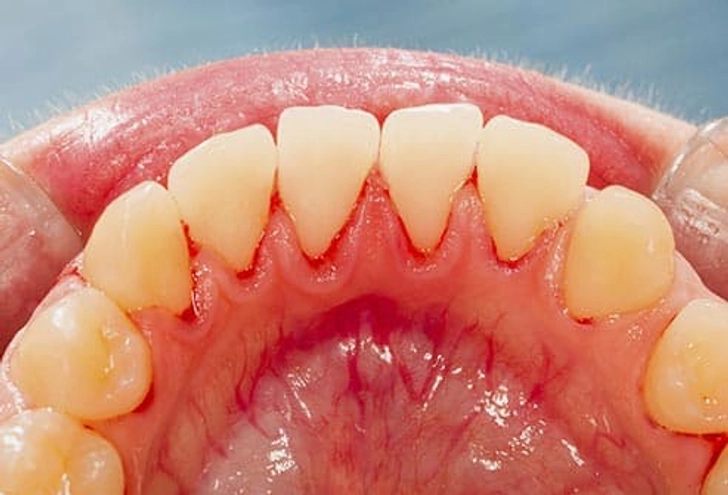

۱۱. مشکلات لثه

اگر لثههایتان به راحتی خونریزی میکنند، حساس هستند یا عقبنشینی کردهاند، احتمال بیماری لثه (Gingivitis) وجود دارد. پلاک زیر خط لثه عامل اصلی است. اگر درمان نشود میتواند منجر به از دست رفتن استخوان، لق شدن دندانها و مشکلات گفتاری یا جویدن شود. پیشگیری شامل مسواک، نخ دندان، دهانشویه آنتیسپتیک و جرمگیری منظم است.